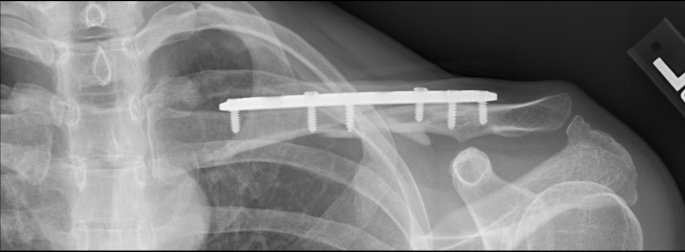

- Broken left collar bone after falling off my bike. (bridge over Adobe Creek on East Bayshore Rd)

The bone was too badly shattered to allow natural healing, so I had a metal plate inserted 10 days after the break, with bone putty to try to guide and speed up bone regeneration. The screws holding the plate backed out and abraded inside of skin, so the same doctor removed the plate after 6 months. The bone broke again 6 days later under light use. A new surgeon worked to fix it by running a threaded rod put down the center of the bone, held in position by a "nut" that sticks out of the back of the shoulder joint. (This is a fairly new procedure and has only been in general use for 1-2 years.) That pin pierced the collarbone and wound up sticking out the front of the bone, threatening to puncture the skin and creating a "teeter-totter" effect for the two halves of my collarbone (preventing rejoining). The surgeon went back again, removed the original pin, and rethreaded a new, longer pin down the back of the two halves of the bone. So far, this seems to be working well (fingers crossed). I will need to go back for more surgery in 12-24 months to have the pin removed.